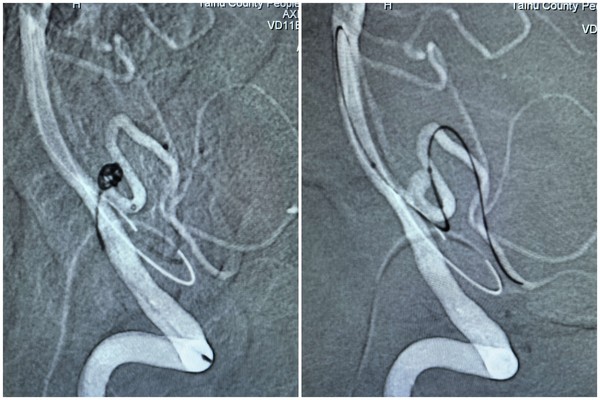

WPS拼图术中10.jpg

为制定最优手术方案,医院术前多次组织多学科病例讨论:影像科利用三维重建技术,清晰呈现动脉瘤与周围血管的解剖关系,为手术定位提供精准依据;麻醉科结合患者高血压病史,量身定制 “术中血压精准调控” 方案,保障手术安全;介入团队则通过模拟手术操作流程,确定 “先填弹簧圈、再放颅内支架” 的分步策略,有效避免单一栓塞材料无法完全隔绝瘤腔的问题。​

手术当天,在 DSA 设备实时引导下,介入医生先为患者进行右侧股动脉、右侧桡动脉穿刺置管,成功建立双通道。随后,通过股动脉通路,利用翻山技术将支架微导管置入右侧小脑后下动脉;同时通过桡动脉通路,将弹簧圈微导管精准送入动脉瘤腔内。团队先填入几枚不同规格的弹簧圈,再沿支架微导管释放一枚颅内支架,实现对动脉瘤的完全覆盖。术中造影显示,动脉瘤已完全隔绝,基底动脉、右侧小脑后下动脉血流通畅,未出现血管狭窄或栓塞迹象,整个手术历时 2 小时顺利完成。​